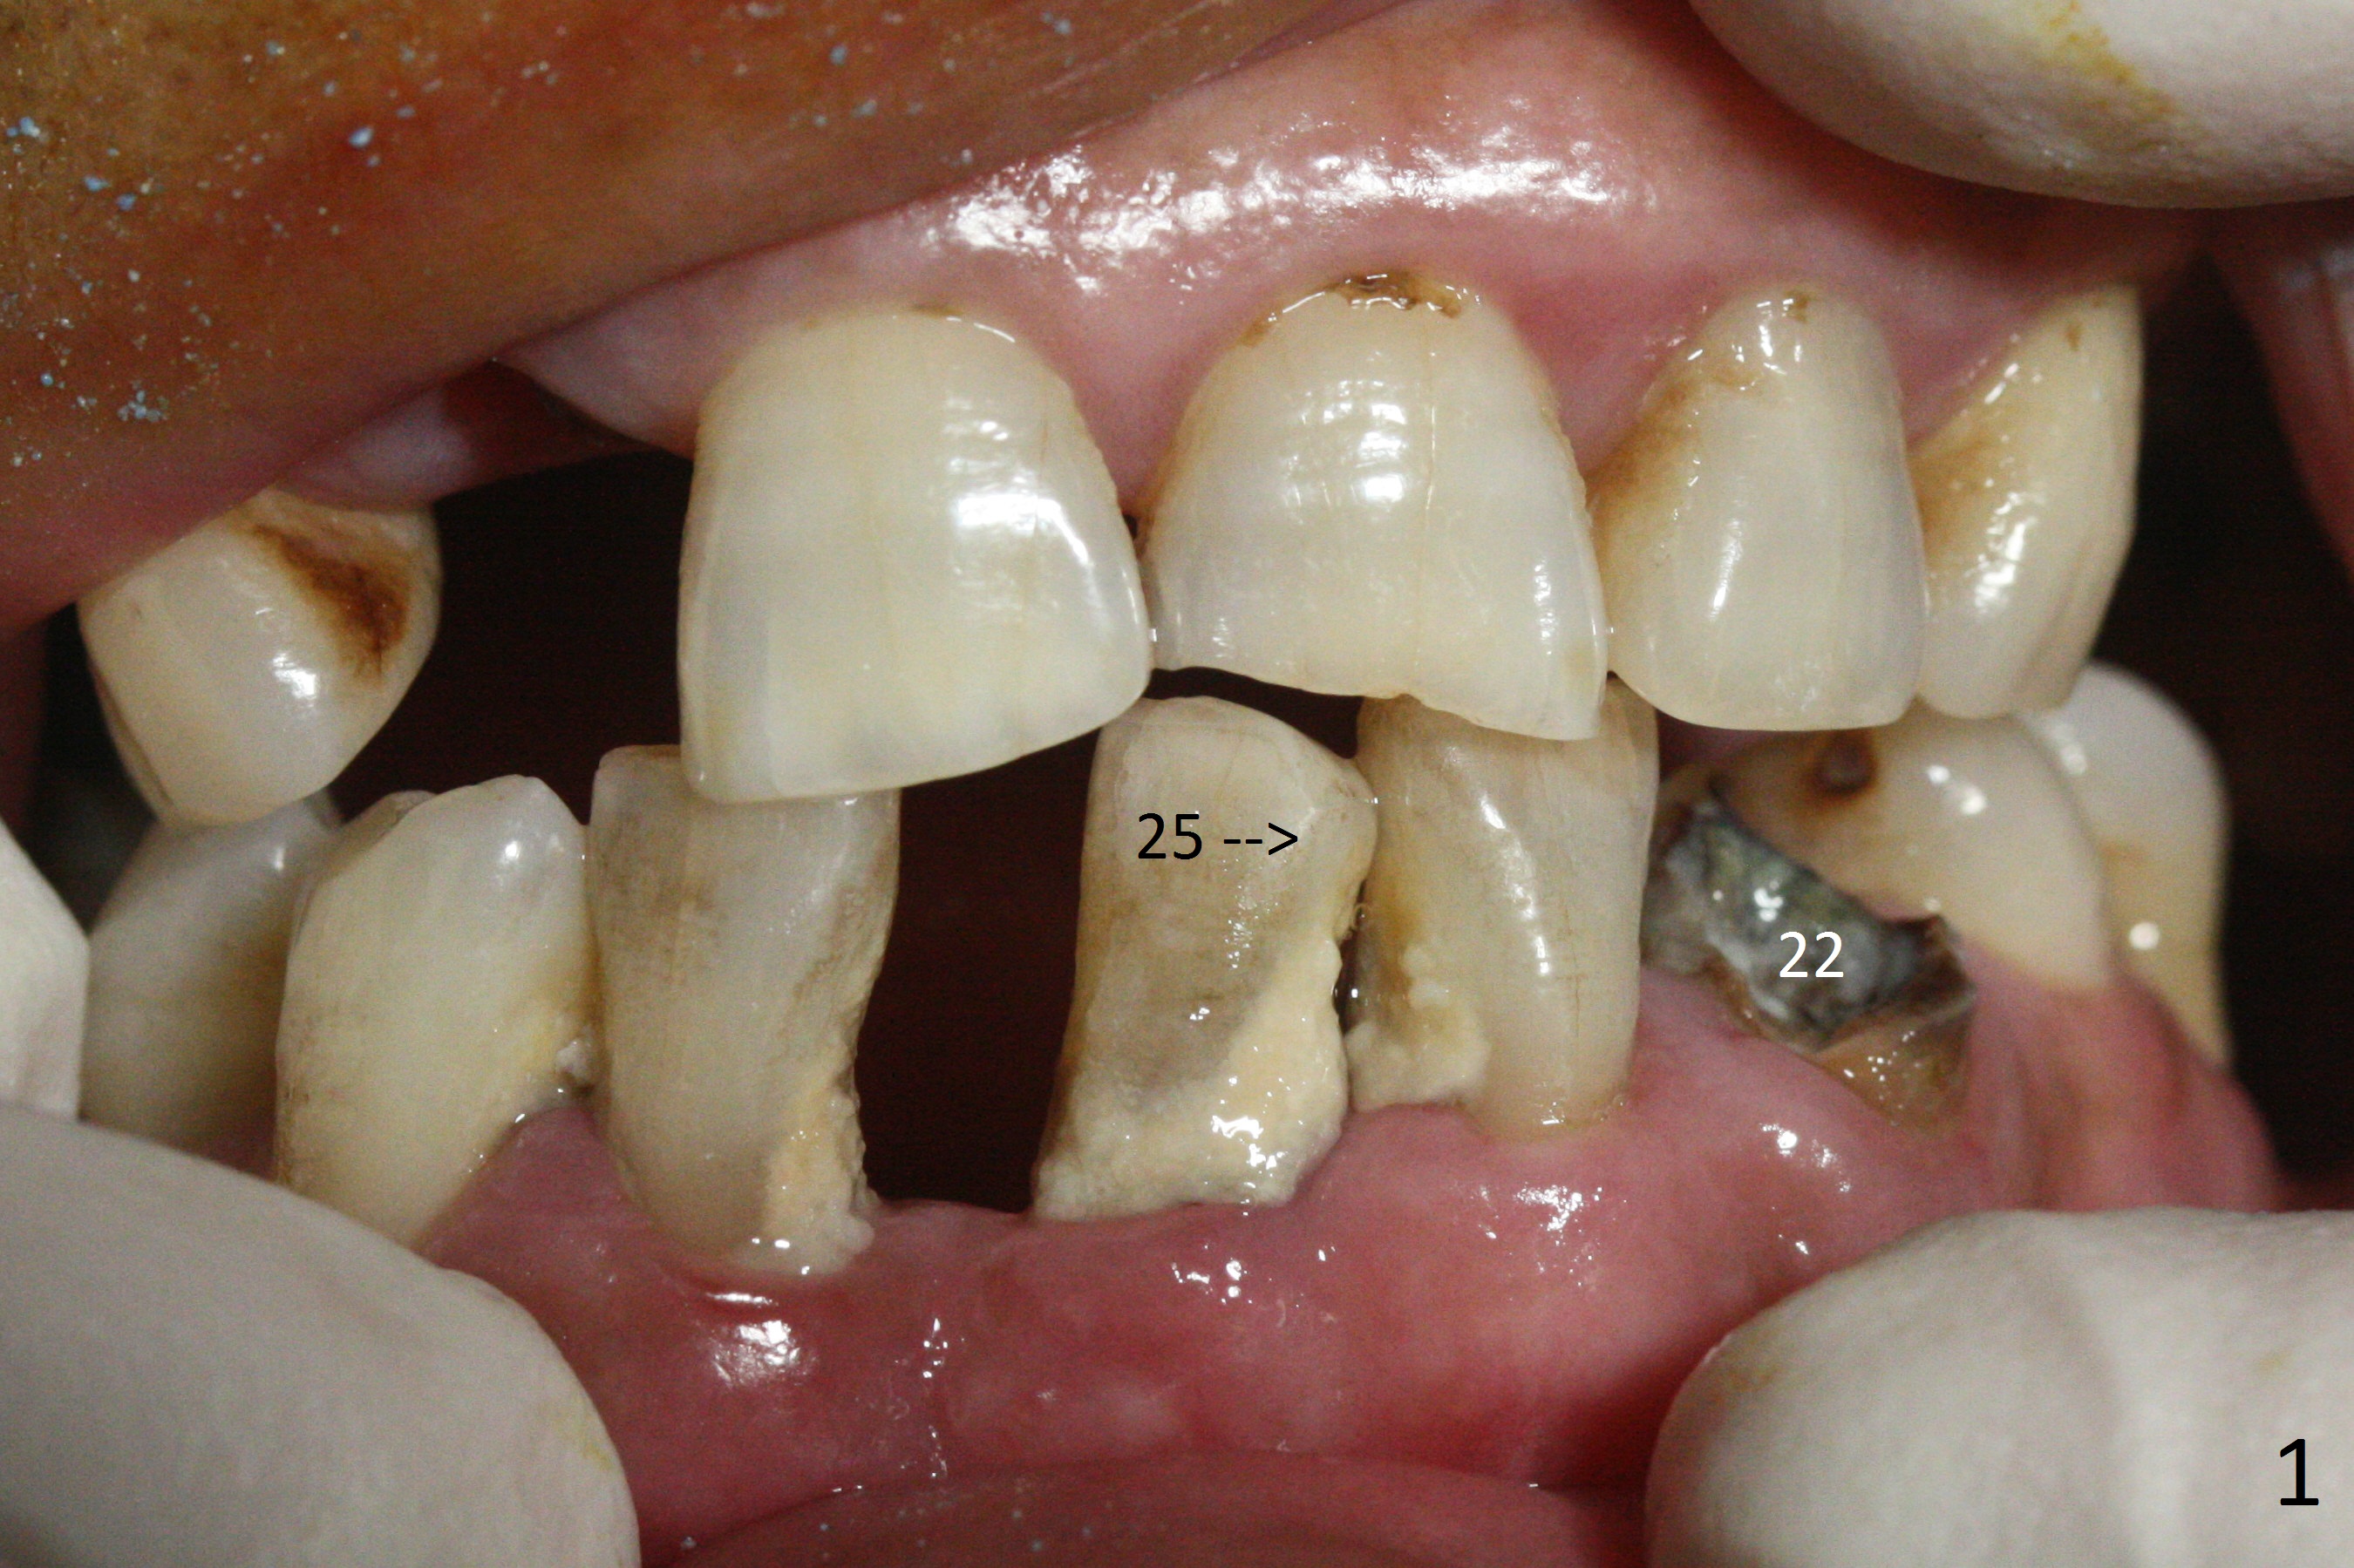

The depth of the osteotomy at #22 is 2-3 mm more than the expected implant length (Fig.2 with 2.7 mm drill in place). The implant at #22 (3.8x18 mm with insertion torque more than 50 Ncm) has clearance from the Incisive Canal and Mental Loop (Fig.3 red dashed line). Allograft with Osteogen is placed around the implants (Fig.4 *) in addition to Osteogen plug (cut in a thin layer) placed against the buccal wall of the socket at #22 (potential leakage). After suturing (Fig.5) and provisional cementation (Fig.6), periodontal dressing is applied (Fig.7). The implants seem to be ready for impression 4 months postop (Fig.8).